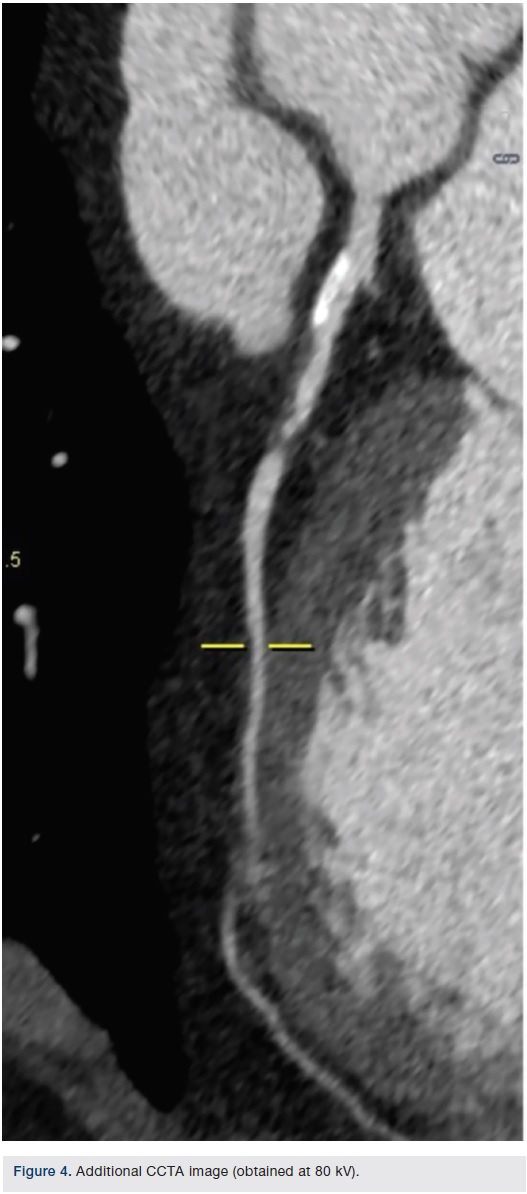

The SOMATOM Force CT system (Siemens Healthcare), which enables fast temporal resolution, was used to perform a coronary CT angiogram (CCTA) on an emergency department patient. The CCTA displayed a 90 percent or greater non-calcified short stenosis in the mid left anterior descending coronary artery (LAD). The next day, the patient’s coronary catheterization revealed a mid-LAD stenosis, type B1 and ulcerative, just distal to a moderate-sized diagonal. A drug-eluting stent was placed; no residual stenosis and normal distal flow was observed. A day after stent placement, the patient was discharged.

Images/courtesy St. Elizabeth Hospital, Edgewood, Kentucky